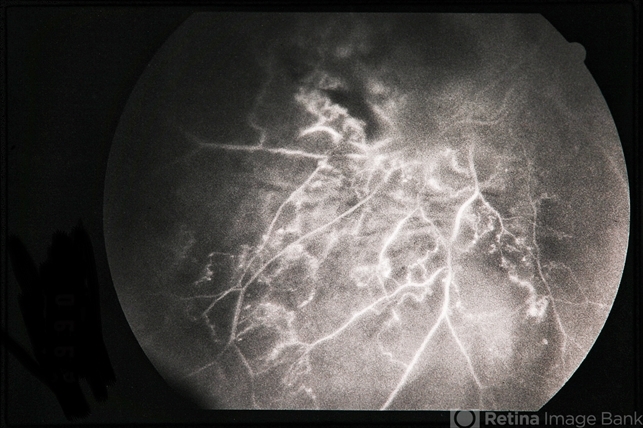

BRVO - Massive Exudate from Collaterals

branch retinal vein occlusion (BRVO), exudate, collaterals

66-year-old female with BRVO - massive exudate from collaterals, 20/70 OD; 20/25 OS in 1985; +HTN, glaucoma; 20/200 OD 1987.